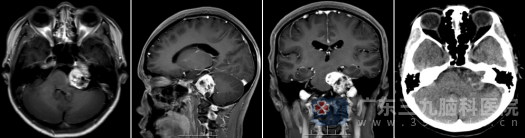

入院后,神经外十科团队为王某安排了详细的前庭功能及听力评估,并进行了头颅MRI检查。结果显示:左侧桥小脑角区可见一范围约33×29×34mm的团块状异常信号影,并突入左侧内听道。结合影像学特征,专家团队诊断为:听神经瘤(前庭神经鞘瘤)。

手术在高清显微镜及神经电生理监测下进行,以最大限度地保护面神经和听神经功能。经过数小时的精细操作,肿瘤被完全切除。术后复查MR提示:肿瘤无残留,已完全切除。术后病理结果也证实了术前判断:(桥小脑角区肿瘤)神经鞘瘤, CNS WHO 1级,属于良性肿瘤。